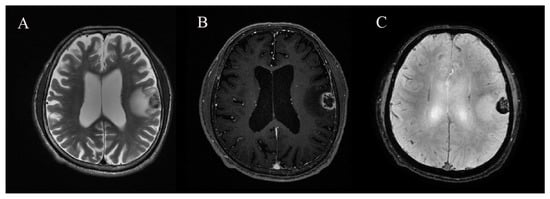

2.2. MRI and Image Analysis